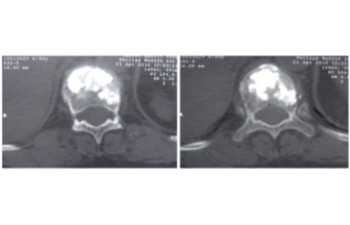

Cas clínic d'una resecció (corpectomia) i reconstrucció vertebral lumbar en una fractura esclat de nivell L4.

En els casos de les fractures més greus, com les fractures conminutes i les fractures d’esclat, un fragment del cos vertebral pot ficar-se dins del canal medular, provocant una compresió de les estructures neurològiques (estenosi del canal medular).

Quan amés n’hi ha un compromis neurològic, s’haruá de realitzar una resecció parcial o total del cos vertebral fracturat (corpectomia) per després reconstruir-lo reconstrucción mitjantçant d’una caixa somàtica expandible. La reconstrucció es sol completar amb una artrodesi percutànea instrumentada i cementada dels nivells adjacents a la fractura. La resecció de la vèrtebra (corpectomia) permet extrahir el fragment d’os qu’es trova al canal medular i lliberar les estructures neurològiques afectades. La reconstrucció amb una caixa somàtica permit descarregar la carga del pacient sobre la fractura i treure el dolor que aquesta li provoca.